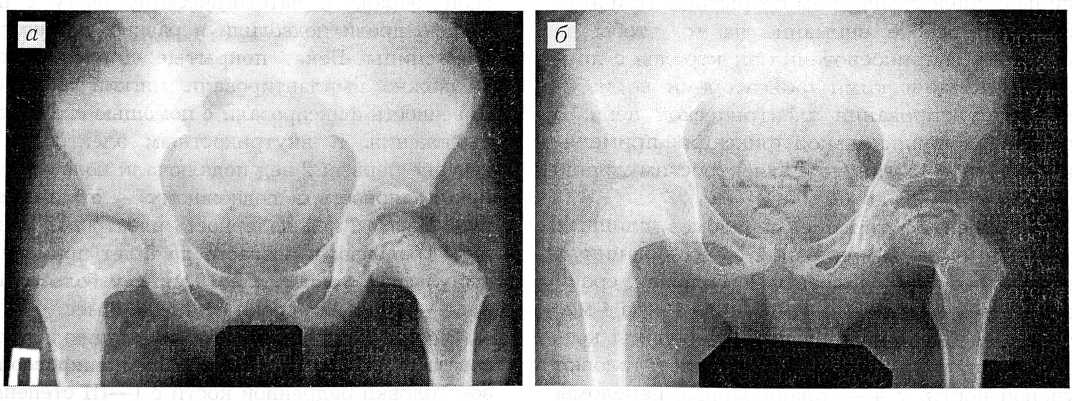

Рентгенограммы больного с III стадией болезни Легга—Кальве—Пертеса. а — до начала, б — через 3 мес после лечения ИЭТ.

Применение электростимуляции у 3 больных с импрессионным переломом при болезни Легга—Кальве—Пертеса в сроки от 1,5 до 3 мес способствовало перестройке костной структуры и прекращению патологического процесса в головке бедренной кости. В III стадии заболевания уже на 4—5-й неделе воздействия импульсными токами в патологической зоне начиналась умеренная перестройка костной структуры, которая достигала максимума к концу 3-го месяца стимуляции остеогенеза. Рентгенограммы больного с III стадией заболевания до начала лечения и через 3 мес после воздействия ИЭТ представлены на рисунке.